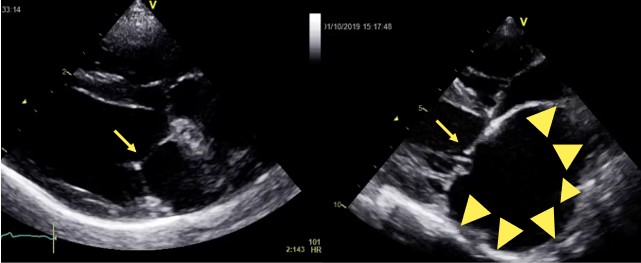

超音波検査 左:正常なワンちゃんの心臓

右:僧帽弁閉鎖不全症のワンちゃんの心臓  右の画像では、心臓のお部屋が非常に大きく拡大、僧帽弁(矢印)はボロボロに変性している。診断や評価には心臓超音波検査が有効です。